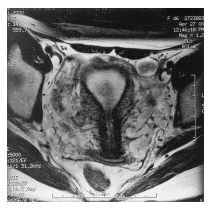

在详细的病史询问和体格检查后,进行超声、CT、MRI、磁共振下血管造影(图19-3)、腹腔镜等检查均有助于盆腔静脉淤血综合征的诊断。影像学检查常同时发现其他异常表现,例如盆腔超声检查发现多囊卵巢(56%盆腔静脉淤血综合征患者合并多囊卵巢)、子宫腺肌症患者。生殖器官静脉造影可以了解盆腔静脉淤血综合征患者静脉曲张的程度(图19-4)。股静脉或颈静脉穿刺插管成功、造影显示左侧卵巢静脉后不立即置入导管,以避免漏诊胡桃夹综合征。在左卵巢静脉附近的静脉血管内注射造影剂,同时患者直立位做Valsalva动作,观察是否存在左卵巢静脉血液返流,如果未发现血液返流,盆腔静脉淤血综合征诊断可能性小,从该点向右卵巢静脉内置管,如果无法快速置管或未见血液返流,则可能无静脉返流存在或返流的程度轻,可以结束检查。如发现存在明显的左卵巢静脉返流(返流的卵巢静脉直径大于8mm),盆腔静脉淤血综合征诊断可能性大。明确盆腔静脉淤血综合征的诊断后如准备进行栓塞治疗需在异常静脉管腔内置管。由于扩张的静脉质地脆,易产生痉挛,操作过程应小心谨慎并间断注入造影剂选择正确的置管路径同时可进一步观察是否合并存在股静脉或阴部静脉的曲张。

图19-3 MRI-T2 盆腔曲张的血管